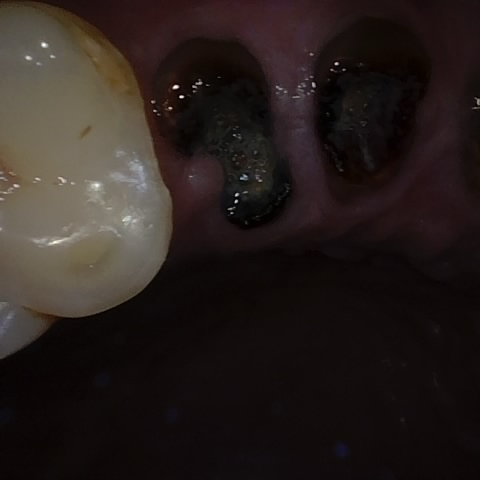

Annotated as "Good"